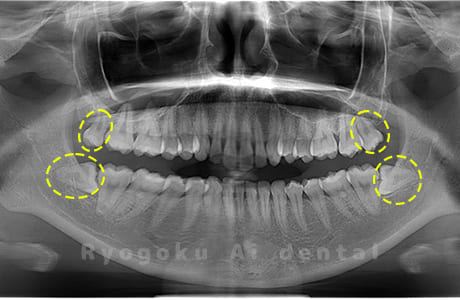

Case03

- 原因

- 上顎、下顎の親知らず

- 治療内容

- 上下4本の親知らずを抜歯したケースです。

<リスク・副作用>

手術後は痛み、腫れ、痺れなどの副作用が生じる場合があります。